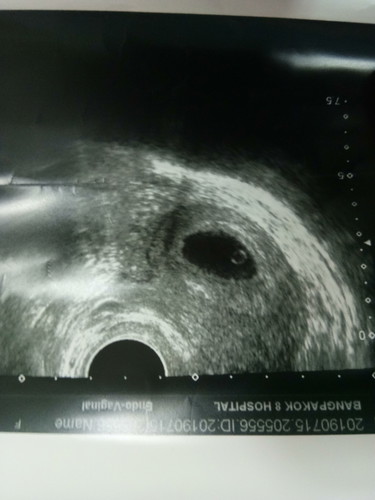

สงสัยท้องลม

จะใช้ท้องลมไหมค่ะ มีเลือดสีน้ำตาลออก9วันท้อง9วีคแต่ล่าสุดที่ไปหมอบอกเด็กยังอยู่ แต่ด้วยความสงสัยทำไมเลือดออกตลอดปวดท้องด้วยจึงไปหาหมออีกที่หนึ่ง หมอบอกว่าน่าจะท้องลมเพราะตามอายุครรภ์น่าจะโตกว่านี้ สับสนไปหมด แต่หมอนัดอีก1สัปดาห์ไปซาวอีกครั้ง